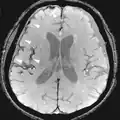

Agentes de contraste

A ressonância magnética para imagens de estruturas anatômicas ou fluxo sanguíneo não requer agentes de contraste, pois as propriedades variáveis dos tecidos ou sangue proporcionam contrastes naturais. No entanto, para tipos de imagem mais específicos, os agentes de contraste intravenosos mais utilizados são baseados em quelatos de gadolínio.[18] Em geral, esses agentes se mostraram mais seguros do que os agentes de contraste iodados utilizados na radiografia ou TAC. As reações anafilactóides são raras, ocorrendo em cerca de 0,03 a 0,1%.[19] De particular interesse é a menor incidência de nefrotoxicidade, em comparação com os agentes iodados, quando administrados em doses usuais. Isto fez uma varredura de ressonância magnética contrastante uma opção para pacientes com insuficiência renal, que de outra forma não seriam capazes de ser submetidos a TAC com contraste.[20]

Embora os agentes de gadolínio se tenham revelado úteis para pacientes com insuficiência renal, em pacientes com insuficiência renal grave que requer diálise, existe o risco de uma doença rara mas grave, fibrose sistêmica nefrogênica, que pode estar ligada ao uso de certos agentes contendo gadolínio. O mais frequentemente ligado é a gadodiamida, mas outros agentes também foram ligados.[21] Embora uma ligação causal não tenha sido definitivamente estabelecida, as diretrizes atuais nos Estados Unidos são que os pacientes em diálise só devem receber agentes de gadolínio quando essenciais e que a diálise deve ser realizada o mais rápido possível após a varredura para remover o agente do corpo prontamente.[22][23] Na Europa, onde mais agentes contendo gadolínio estão disponíveis, uma classificação dos agentes de acordo com os riscos potenciais foi liberada.[24][25] Recentemente, foi aprovado um novo agente de contraste chamado gadoxetate, Eovist de marca (US) ou Primovist (EU), para uso diagnóstico: isso tem o benefício teórico de um caminho de excreção dupla.[26]

Sequências

Uma sequência de RM (Ressonância Magnética) é uma configuração particular de pulsos de radiofrequência e gradientes, resultando em uma imagem específica.[65] O ponderamento T1 e T2 também podem ser descritos como sequências de RM.

| Grupo | Sequência | Abreviatura | Física | Distinções clínicas principais | Exemplo |

|---|---|---|---|---|---|

| Realce de contraste dinâmico | DCE | Medidas de mudanças ao longo do tempo no encurtamento da relaxação spin-lattice (T1) induzido por um bolo de contraste de gadolínio.[85] | O aumento rápido do contraste de gadolínio, juntamente com outras características, sugere malignidade.[86] |  | |